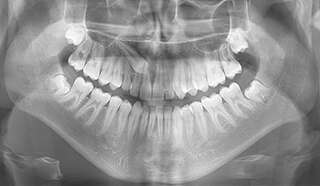

CANINES INCLUSES